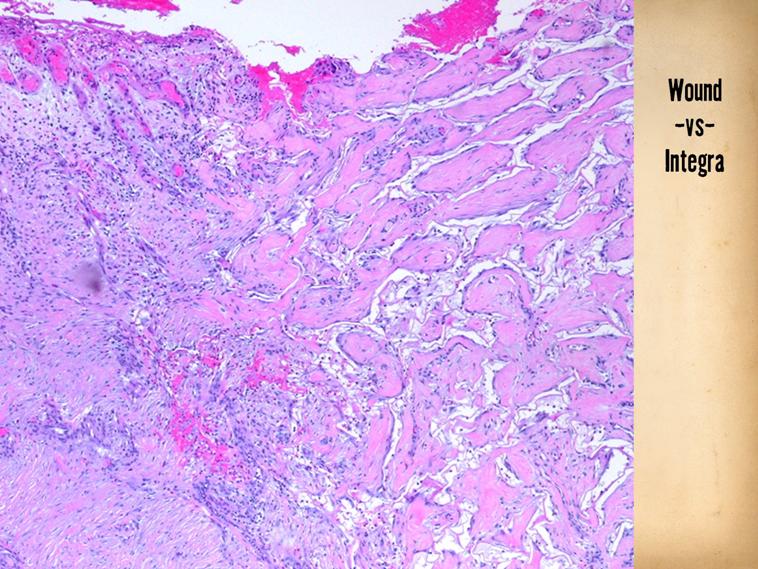

This young woman had strep N.F., beginning around the knee.  The extremity is shown at a point where, after a week or two of care, the wounds are ready for closure.  Drainage incisions of the thigh and leg are closed by simple repair.  To avoid contractures or other scar problems across a joint, Integra was used to reconstruct the missing skin.  It is shown a week or two after placement, a few weeks later when fully regenerated and ready for split thickness overgrafts, and a few weeks after completing the reconstruction.

RIGHT LOWER - Strep fasciitis of the lower extremity, after drainage and debridement, and a week of good wound care, ready for closure.  Simple incisions of the thigh and leg are closed by simple repair.  Missing skin at the knee required an alternate method (Integra CGM was used, discussed on later slides).